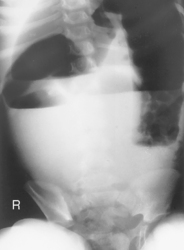

AP supine and AP erect critique

• Supine, legs extended, arms at sides

• Midsagittal plane aligned and centered to centerline

• Ensure no rotation (ASISs equal distance from tabletop)

• Center of IR to level of iliac crests, ensuring that upper margin of symphysis pubis is included on lower IR margin. (A large hypersthenic patient may require that the IR be placed crosswise with a second IR centered higher.)